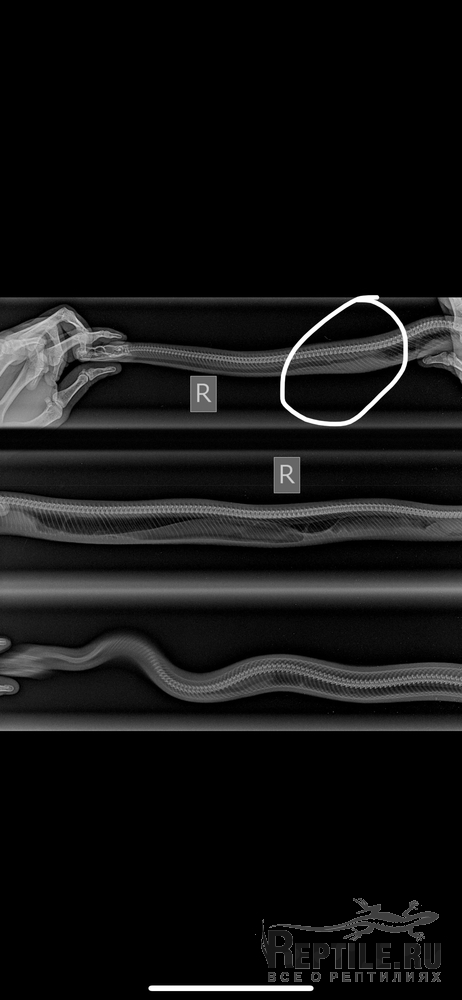

Поставили диагноз травма трахеи. Колю Байтрил. Питон тяжело дышит, иногда со свистом вялый, без аппетита. Первые дни заболевания весь вздулся и была кровь в пасти.

В первый день заболевания заметила после линьки кусками, что у змеи раздувается подбородок и как будто выходит воздух